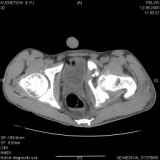

Уважаемые коллеги! Хотелось бы услышать совет по тактике лечения представлленого больного.Поступил после лечения в одном изотделений области. Травма 2,5 месяца назад. После выведенияиз шока был произведен остеосинтез перелома бедра, предплечья, до перевода к нам проводилосьвытяжение по оси шейки бедра за стержень, введенный в большой вертел. На сегодня деформацияригидна, клинически мобильности не определяется. Заранее признателен. P.S. Данный вид травм не включен в перечень "высокотехнологичных операций", направить длялечения по квотам Минздрава очень сложно.

Привет, Леонид. Оскольчатый высокий двухколонный перелом в такие сроки трогать не надо, т.к. это про такие переломы сказано: "кто с ножом на Ж. пойдет тот в ней и останется...".

Может быть неплохой результат при консервативном лечении и ранних движениях.

Если заболит после начала нагрузки в 4-6 месяцев - эндопротез.